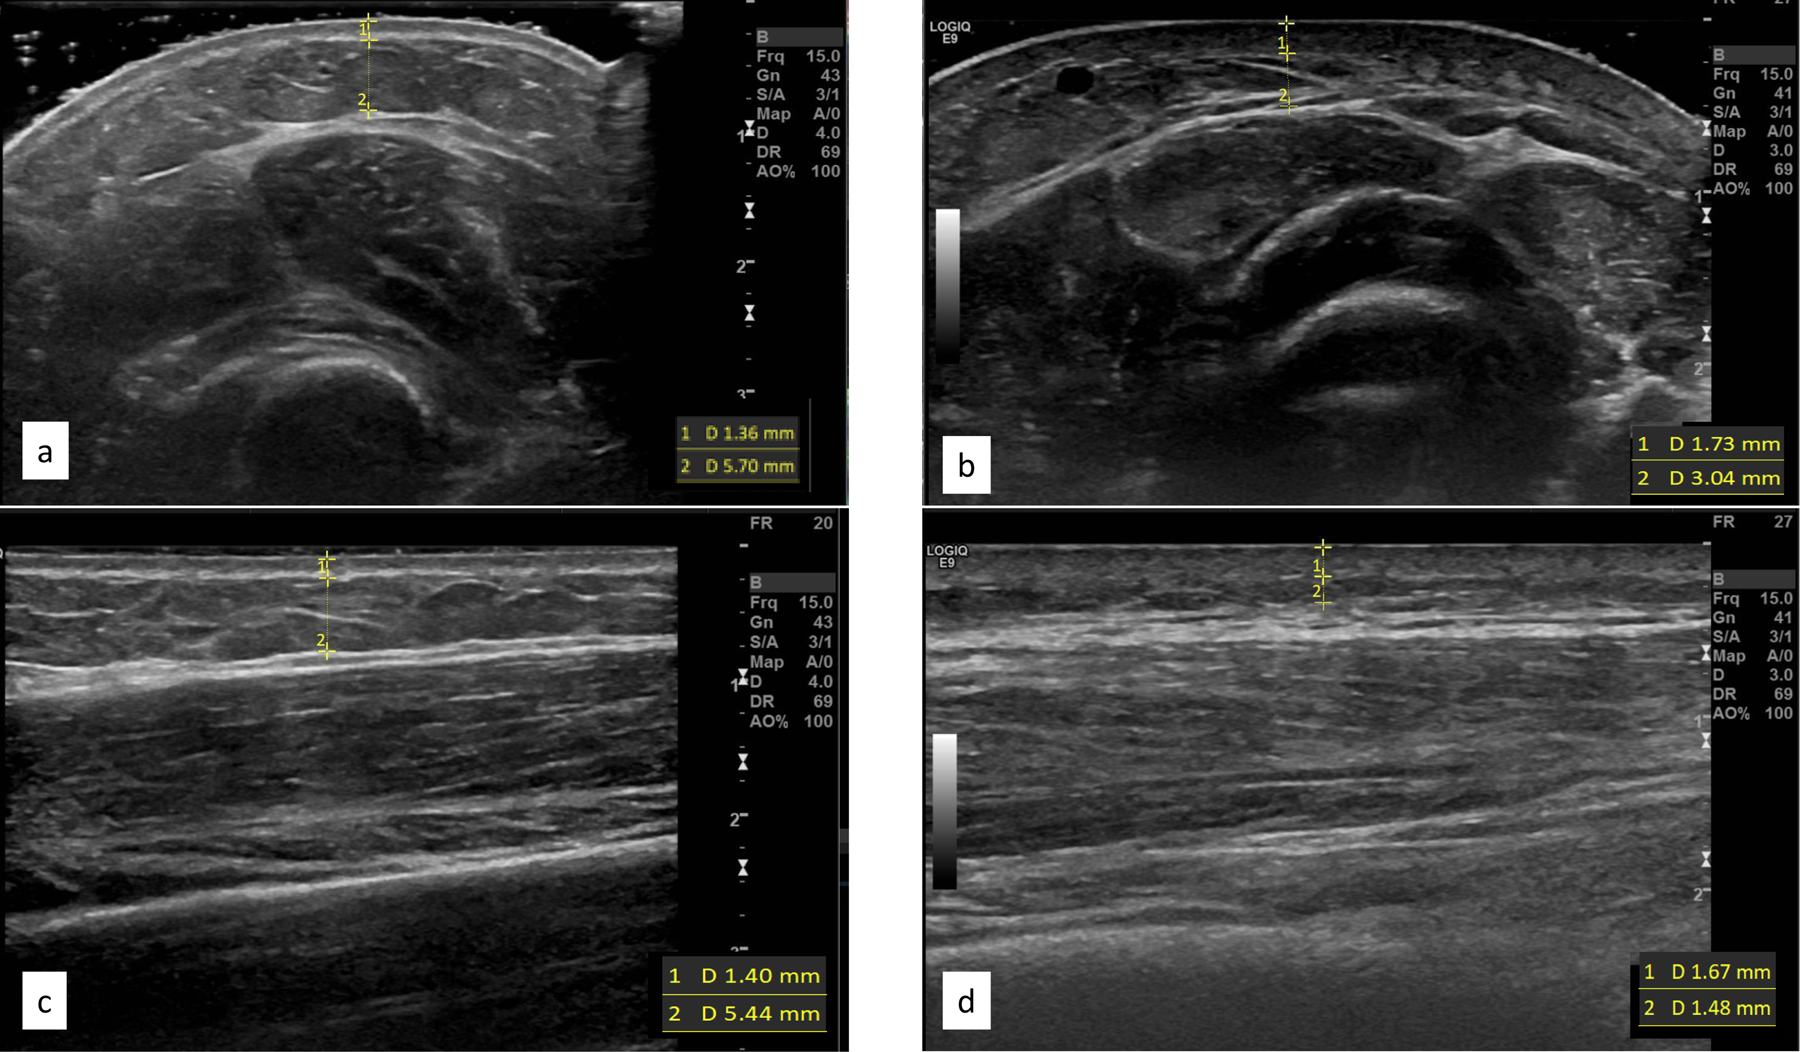

Image acquisition was conducted with the transducer in both transverse (short-axis) and longitudinal (long-axis) planes using grey-scale, color Doppler, and strain elastography at each of the three sites. Grey-scale images were obtained using two techniques to identify the most valid and useful acquisition protocol for examination of dermal and subcutaneous thickness (Figure 2). First, as noted in documented recommendations23, copious gel was used to allow the transducer to float without causing tissue compression. Second, the transducer was allowed to sit on the skin surface while the radiologist was cautious not to apply any additional pressure beyond weight of the transducer itself. Color Doppler was used to examine vascularity or blood flow changes within the subcutaneous soft tissue, muscles, or tendons at each treatment site; the number or intensity of colored pixels indicates amount of active blood perfusion24. Strain elastography images were obtained using a free-hand technique by the radiologist in which a gradual, uniform, and repetitive manual compression was applied through the transducer25; tissues’ elastic properties are reflected in colors assigned to each pixel with a scale ranging from red-softest tissue with high elasticity, to blue-hardest, minimal elasticity tissue structure26.

Figure 2.

Grey-scale images of the forearm demonstrating floating of transducer in cross sectional plane (a) versus transducer on the surface in the same place (b), as images in the longitudinal planes floating and surface (c, d respectively). Borders and measures for dermal and subcutaneous images included

The same two researchers (SR, DMK) independently measured dermal and subcutaneous thickness on each grey-scale image (Figure 2). Dermal thickness was identified as the distance between epidermal entrance echo and the subcutaneous fat from the deep edge of the epidermis to the deep edge of the dermal layer27. Typical dermal layer measurements in normal skin are 1.6 mm, but in SSc it varies from 0.5 – 3 mm27. The subcutaneous layer was recognized as the distance between the deep edge of the dermal layer and superficial edge of the fascial layer of the muscle. Using digital calipers, measurements were taken in millimeters at a rater-selected point within the center one-third of each image where the individual structural boundaries were the most echogenic. The average of three measurements of each layer was recorded, and each rater completed three trials for all measures.